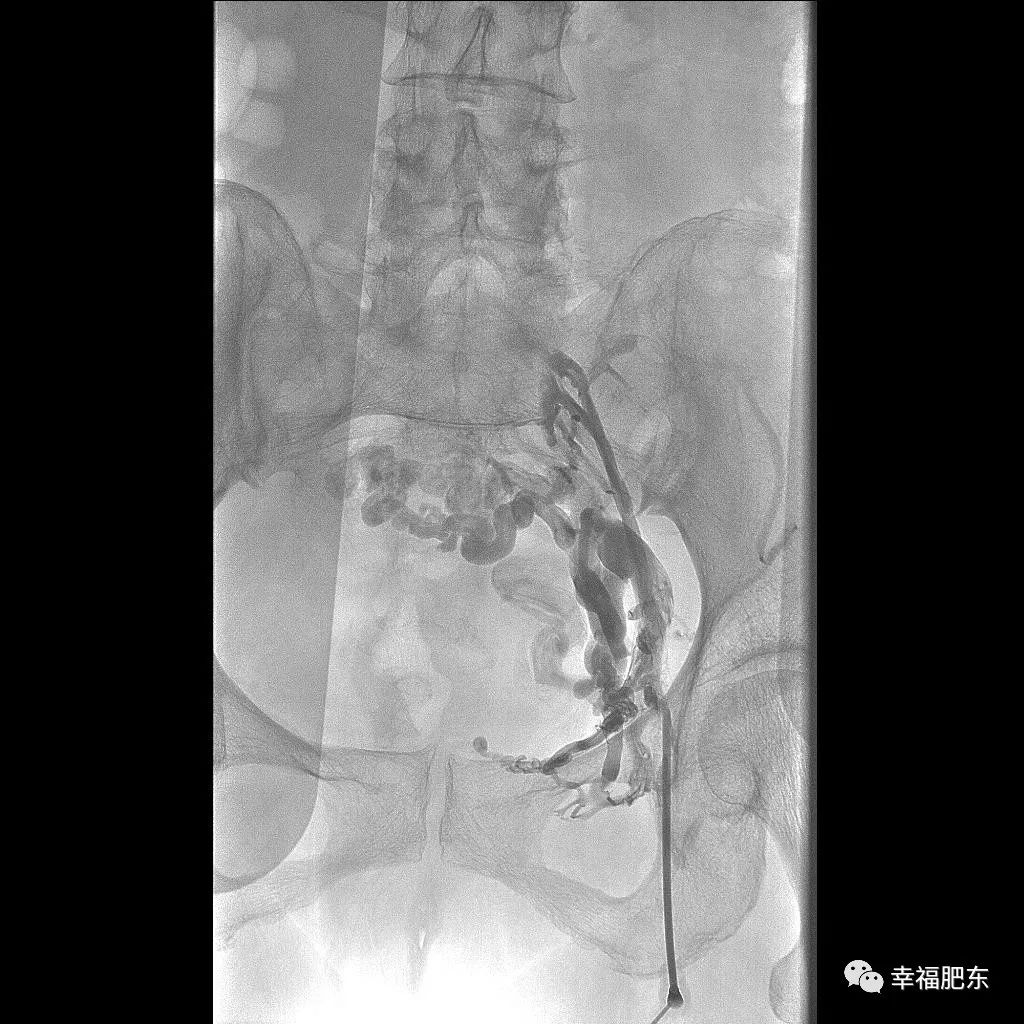

近日,县医院普外科在安医专家余康敏主任的指导下,与放射科、导管室通力协作,利用DSA血管造影机成功实施两例微创介入静脉血管成型及支架植入术,实现县医院血管外科技术水平新突破。

两位患者诊断分别为:左下肢血栓形成后遗症、血管支架内再狭窄可能和左下肢血栓形成后遗症伴下肢静脉性溃疡。以往该类病人得不到彻底治疗,只能在门诊进行创面换药护理、口服药物进行对症处理,病症极易复发甚至加重,该项技术的开展与应用填补了县医院血管介入技术的空白。